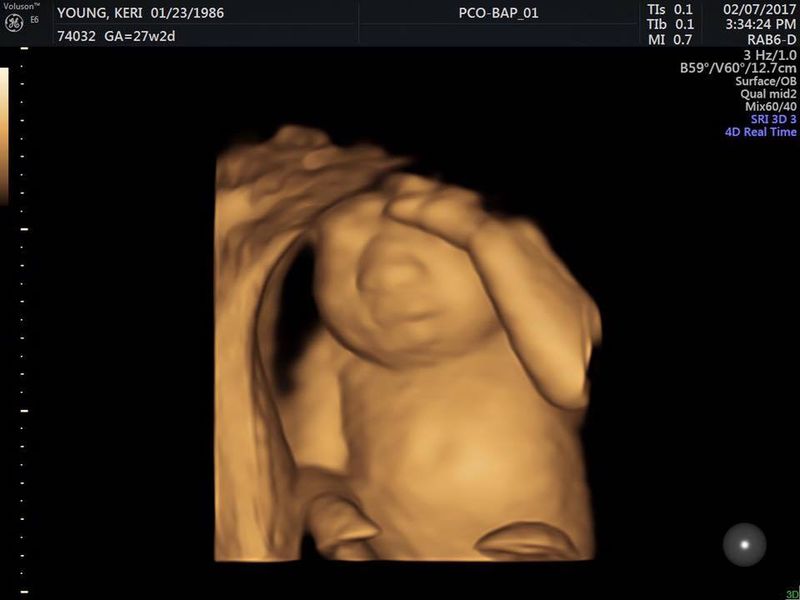

Keri Young era in al noualea cer fiindca a aflat ca urmeaza sa devina mamica, insa fericirea ei a fost umbrita de o veste cumplita. Medicii i-au spus ca bebelusul ei nu are creier.

Keri Young si sotul ei, Royce, isi doreau foarte mult sa devina parinti. Cei doi tineri din Oklahoma City au reusit sa conceapa un bebelus, insa medicii le-au dat o veste cumplita: copilul din burta nu are creier.